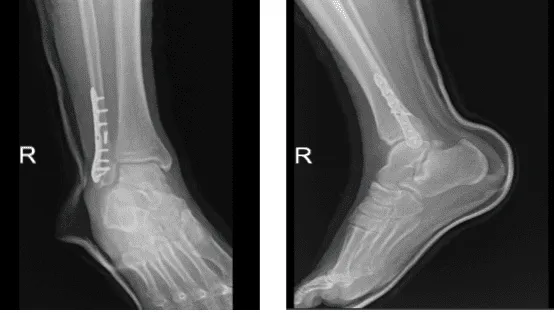

After three weeks from the surgery, the patient went to the office with X-ray results, for his follow up checkup. The skin of the patient peeling over the incision is resolved, the walking boot PWB 25%, to increase gradually with the help of the ice, elevation and OTC anti-inflammatory meds, the patient is doing very well after the surgery.

The surgical plate and screws transfix a fracture of the distal right fibula. Alignment is near anatomical, there is no significant interval change, the distal tibia is intact. There are no significant degenerative changes, the Ankle mortise is well maintained. There is no appreciable soft tissue swelling and no calcaneal plantar spur.

X-ray right ankle – 3 weeks after surgery